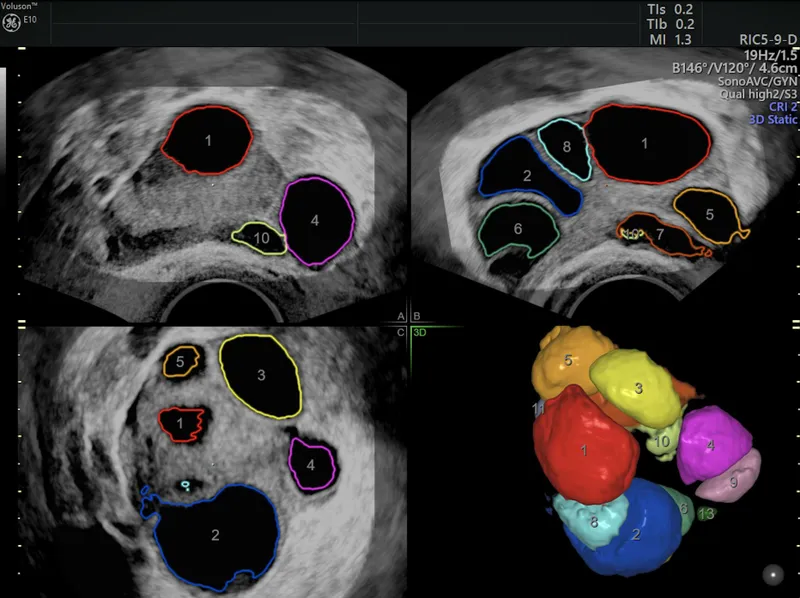

- Transvaginal Ultrasound (TVS): Antral Follicle Count (AFC), uterine/adnexal pathology

- Transvaginal Sonography (TVS): Follicular growth (serial), endometrial thickness (target ≥7-8 mm).